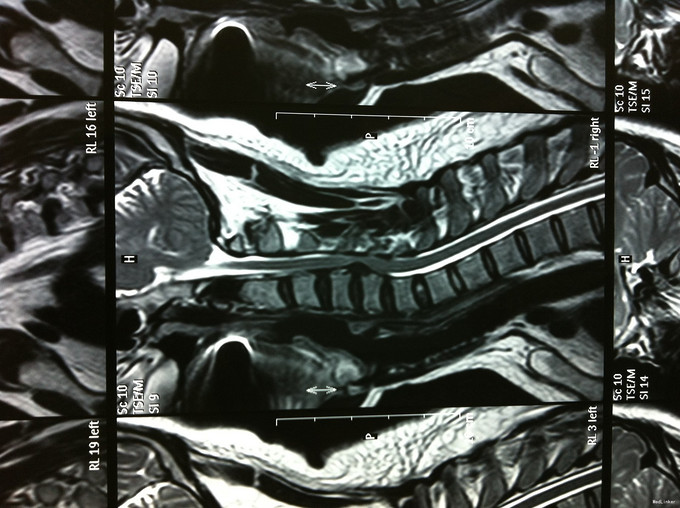

颈肩疼痛1年,加重伴左上肢疼痛、行走不稳1个月 患者1年前无明显诱因出现颈肩部疼痛不适,不伴四肢放射性疼痛、无力,劳累后加重,平卧休息可缓解。1个月前无明显诱因出现颈部疼痛加重,伴左上肢放射性疼痛,行走不稳、双足踩棉感,无高热、寒战,无低热、盗汗。

查体:左侧前臂及手感觉减退,右侧正常,左侧伸腕、伸肘肌肌力4级,右侧伸腕、伸肘肌肌肌力4-5级,双侧霍夫曼综合征阳性,双下肢肌张力高,膝腱反射+++,巴氏征阳性,辅助检查: X-ray:劲椎退行性变 CT及MR:颈椎间盘突出,腰5/6,6/7间盘突出并骨赘形成

诊断:脊髓型颈椎病 处理: 1、完善相关辅助检查,明确诊断,有无手术指证; 2、全麻下行颈椎前路减压,颈椎间盘突出并骨赘形成,行颈6椎体次全切,减压较充分。